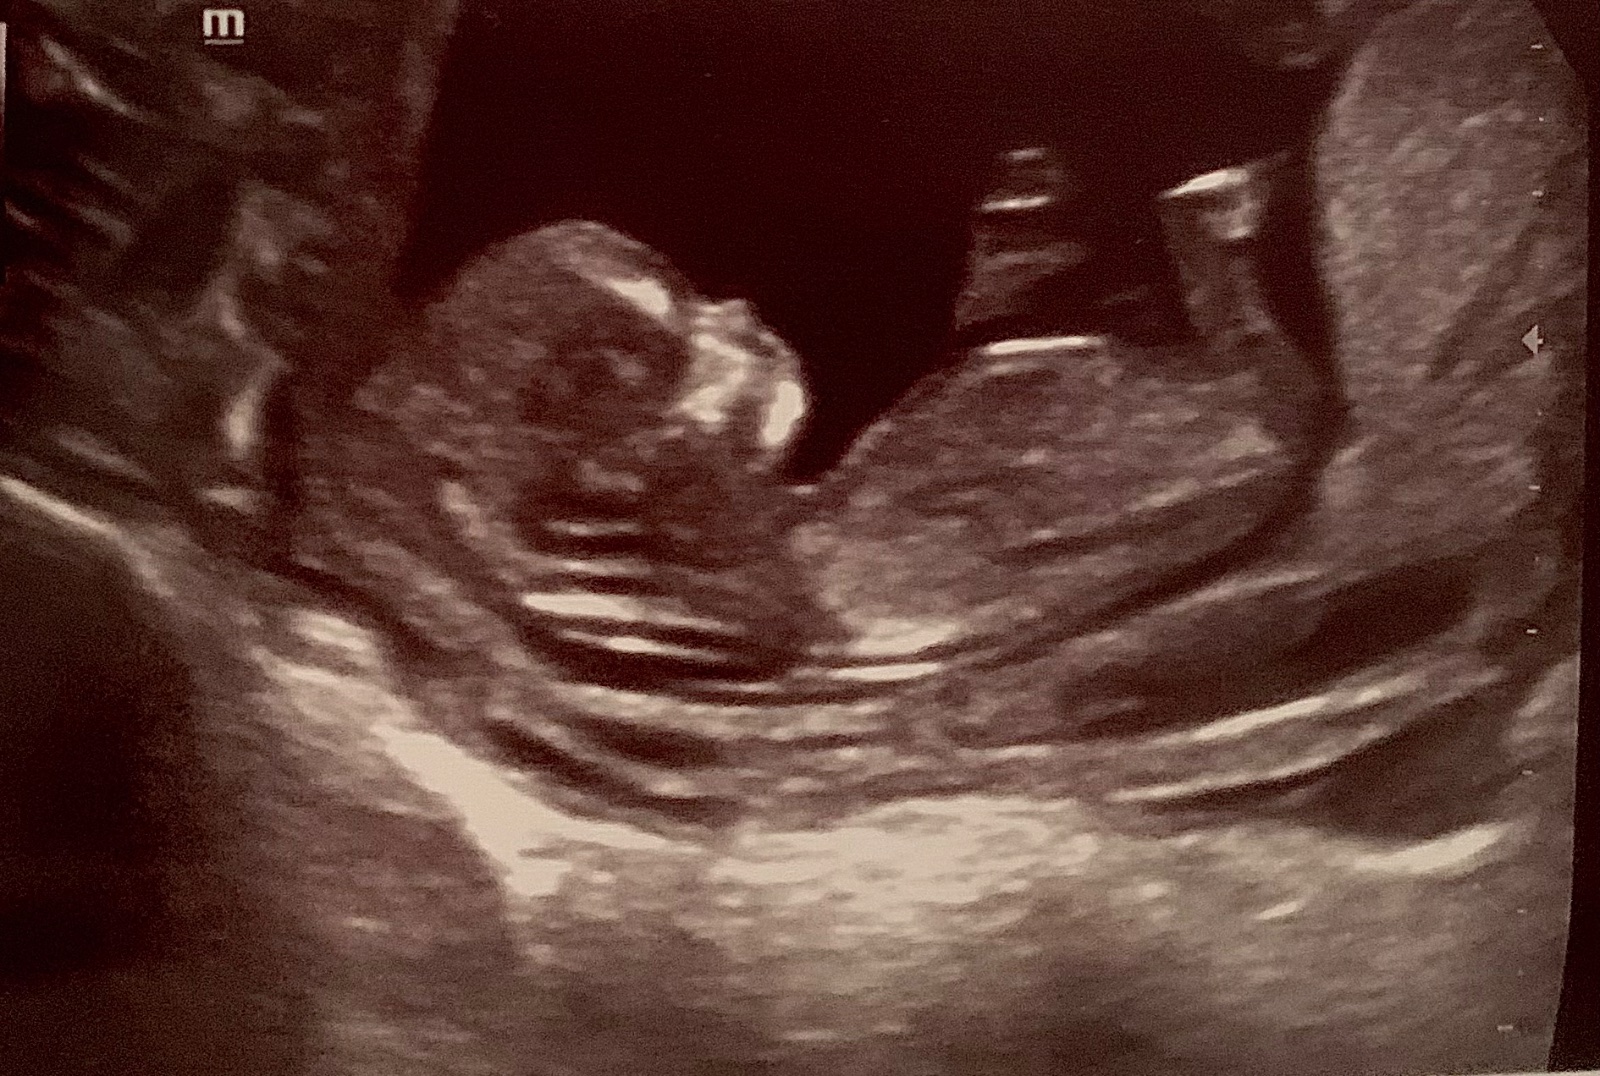

Oplatí sa absolvovať 3D ultrazvuk alebo 4D ultrazvuk?

Výbežok nevidím, podľa skull chlapcek.. aj keď nás by mal byť podľa skull ukážková baba a není, mame výsledky z krvi😅🤣